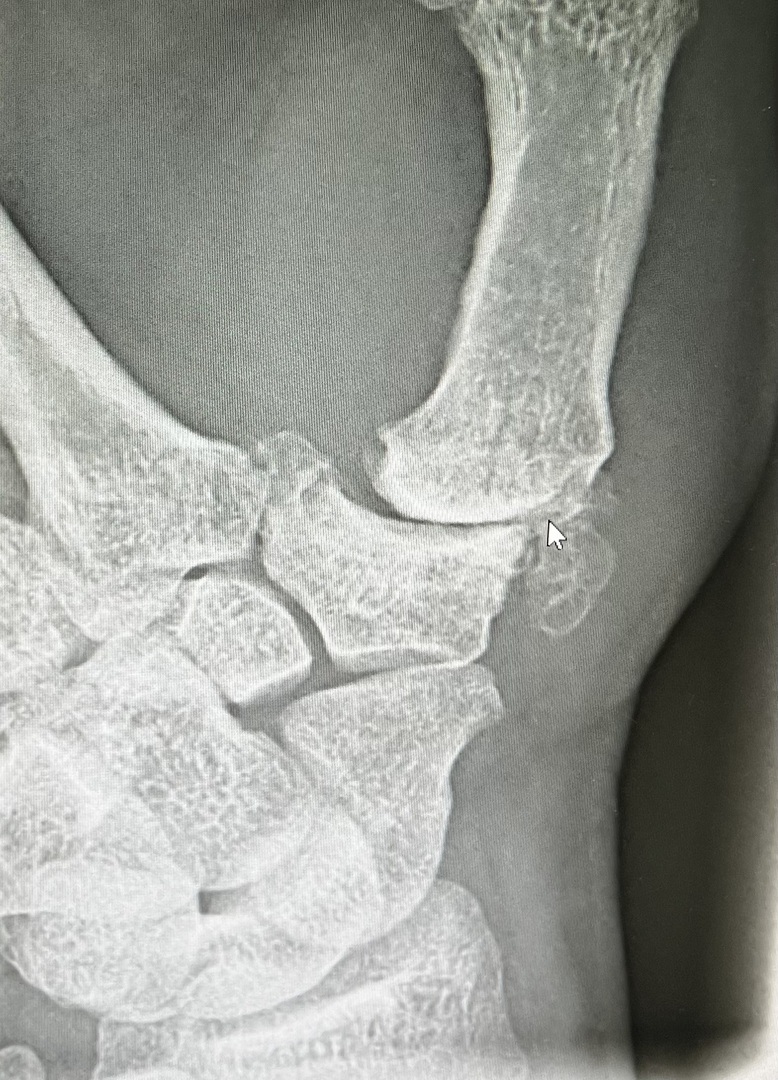

Rhizarthrose / Sattelgelenksarthrose

Die Sattelgelenkarthrose beschreibt einen Knorpel-verschleiß am Gelenk zwischen dem Vieleckbein (Trapezium) und der Basis des

1. Mittelhandknochens. Die ersten Anzeichen treten häufig in Form von Belastungsschmerzen auf, wie z..B. bei alltäglichen Tätigkeiten (Flaschenöffnen, Gläser aufschrauben, Knöpfe öffnen usw.) auf. Zunächst wird konservativ behandelt mit Ruhigstellung einer Orthese, Analgetikatherapie, Spritzen mit Hyaloron oder Eigenblutkomponenten (Plasma, ACP, PRP). Bei Versagen der konservativen Therapie wird die chirurigsche Behandlung empfohlen mit Entfernung des Trapeziums und Bandplastik oder Daumensattelgelenksprothese. Der Eingriff erfolgt in Narkose oder Plexusanästhesie. Nach OP erfolgt eine Ruhigstellung bis ca. 3 Wochen, ggf. Physiotherapie. Wenn eine Prothese eingesetzt wird erfolgt die Ruhigstellung nur wenige Tage. Alltägliche kraftfordernde Tätigkeiten sind in der Regel ab dem 2. Monat nach OP wieder möglich.

Nach Protheseneinbau in unsere Klinik.

Sattelgelenkprothese (Typ:Touch Fa. Medartis)